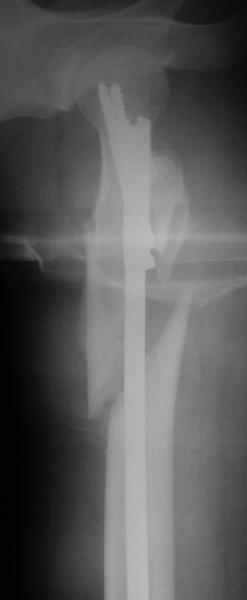

Наверно, можно и так сказать, но можно и тоже самое - 4-фрагментный вертельный перелом. Выбор тот же, но с учетом молодого возраста реконструкционный гвоздь тут более применим. Вот уже наш пример.

Перелом подвертельный. Лечение оперативное, срочное,

PFN с длинной ножкой чтобы избежать стрессовые изменения в будущем. Обычно у молодых людей требуется проводить рассверливание канала как при гвоздевании.

В данной ситуации я бы провел остеосинтез при использовании длинного Gamma Nail

Вправление не было бы идеальным но операция закрытым доступом была бы меннее тяжелой так же как и ее последствия .